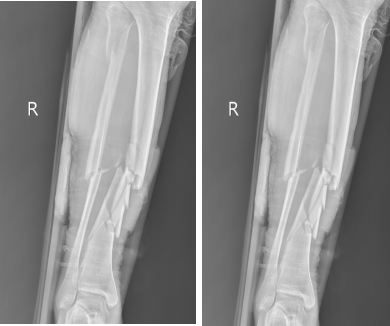

病例分享

67岁的戎先生在家中不慎摔伤,致右胫腓骨开放性粉碎性骨折。

[术前检查]

外固定支架创伤小更有利于术后恢复,对于开放性骨折或感染无法第一时间进行内固定的患者,外固定支架无异于最优选择,外固定支架已广泛应用于治疗骨折、矫治骨与关节畸形和肢体组织延长。